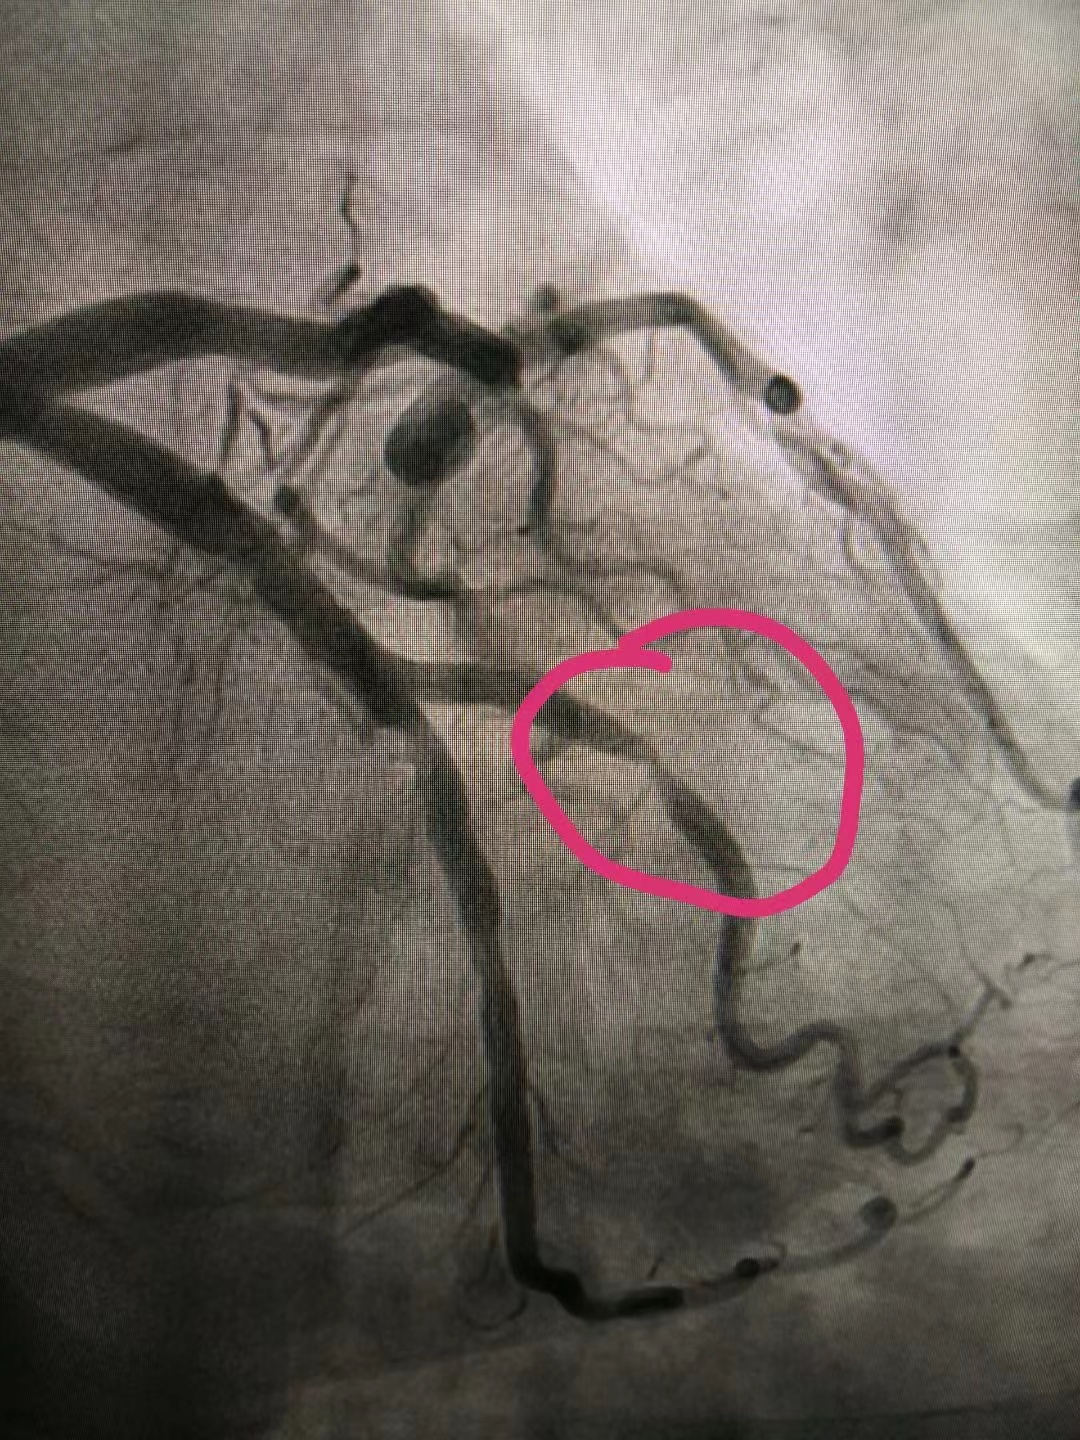

PCI术前

12月18日,70岁的杜大娘因“阵发性胸闷、心悸3天”于门诊急入住心内二科,成为科室成立当天首位住院患者。副主任王涛迅速接诊,为其查体,询问病史,患者心电图示:窦性心律、频发房早。科主任李永平凭借多年临床经验,考虑为急性冠脉综合征,不稳定性心绞痛。情况紧急,李主任与王主任共同评估患者病情后,立即向家属说明病情,并及时联系介入室,进行冠脉造影检查,发现老人回旋支OM2近段80%-90%×8mm狭窄,前向血流TIMI3级,符合PCI(即:经皮冠状动脉介入治疗手术)治疗指征。时间就是生命,在医护人员的缜密配合下,为患者行PCI治疗,并置入支架1枚。患者术中无任何不适,精神状态良好,术后安返病房。住院期间,护理人员严格执行护理核心制度,做好危重冠心病患者的护理工作。为表感激之情,患者家属特意到办公室对心内二科医护人员进行感谢。